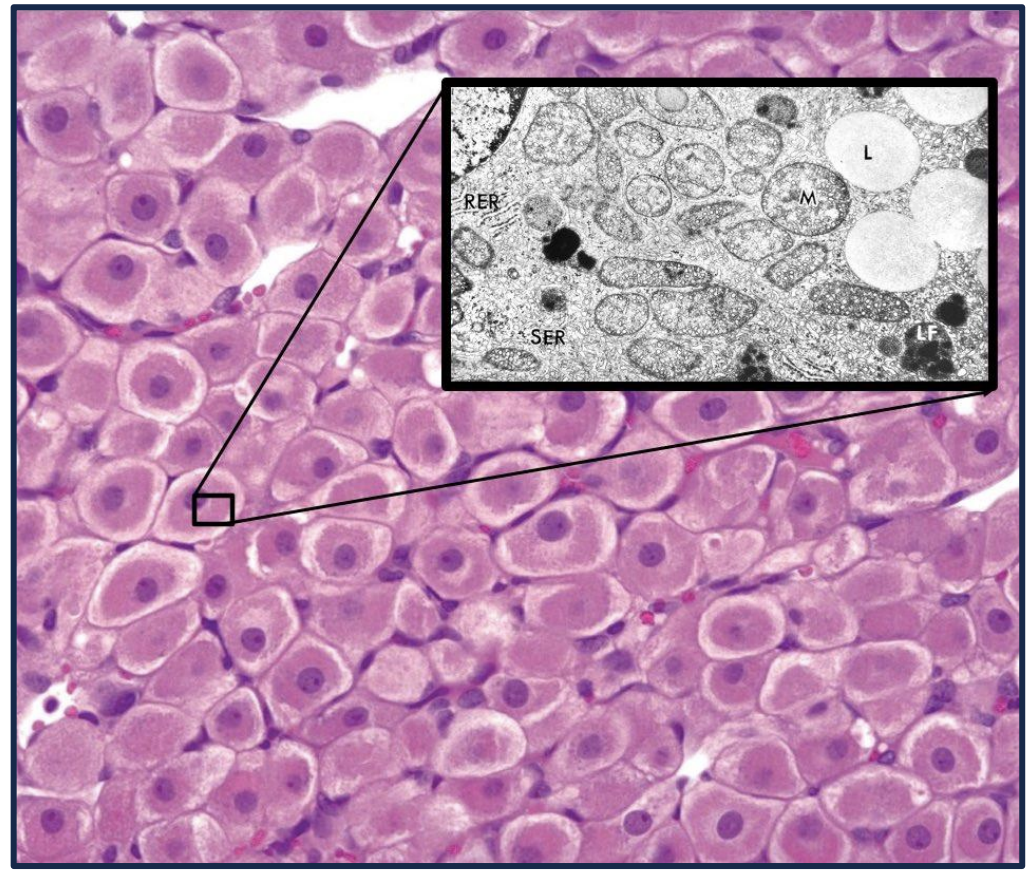

What do these cells secrete?

Steroid hormones

* We can see a white ring around the cell which indicates lots of smooth ER

* Lots of smooth ER means we are either in liver (detox) or a site of steroid production

Leydig cells secrete testosterone into the blood; therefore their structure includes:

Leydig cells secrete testosterone into the blood; therefore their structure includes: * **Lipid droplets** * **Lots of smooth ER** * **Mitochondria with tubulovesical cristae**

46

Leydig cells contain rod-like cytoplasmic inclusions called _

Leydig cells contain rod-like cytoplasmic inclusions called **Reinke crystals**